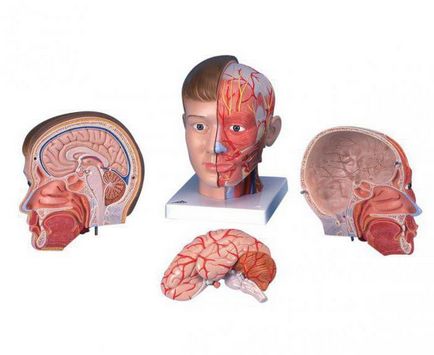

Hogyan működik egy személy: a helyét a szervek. fej

Brain, talán marad a legrejtélyesebb és felfedezetlen testrészt. Minden testrész vonatkozik ez a központ. Az agy a koponyában, védi az erős csontok a koponya. Az agyból az egész szervezetben szórás idegek, amely megkapja pulzusjeleket egyik vagy másik cselekvés. Hála a csapatok az agy látunk, hallunk, úgy érzi, mozog, valóban él és vagyunk.